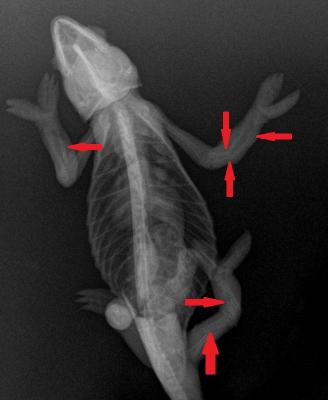

Během léčby se majitelka snažila všemožnými způsoby zabránit dalším zlomeninám. Bohužel, než se kosti zpevnily ukládáním vápníku, došlo ke zlomenině druhé stehenní kosti. Tato zlomenina byla také dislokovaná (na snímku zobrazena červenou šipkou), proto se majitelka rozhodla pro euthanasii.

Na tomto snímku jsou červenými šipkami znázorněny zlomeniny různých kostí. Nejvážnější byla zlomenina stehenní kosti, protože zde se fragmenty překrývaly a tudíž kost neměla šanci srůst.